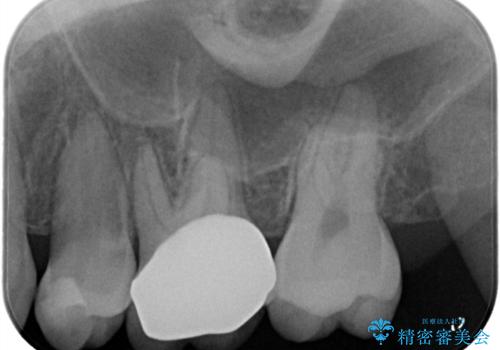

【VPT/歯髄温存療法・オールセラミッククラウン】虫歯が深く神経まで達していたが健康な神経は残す治療!

- 虫歯が神経まで達していたのですが、術前の検査と顕微鏡下で見た神経の状態からVPTの適応と判断し神経を残す治療をしました。

汚染されている神経は除去し残りの神経を残すためVPTを行いバイオセラミックのバイオシーシーラーで充填しオールセラミッククラウンで治療を行いました。治療後2年経過しましたが、神経は温存され経過は良好です。